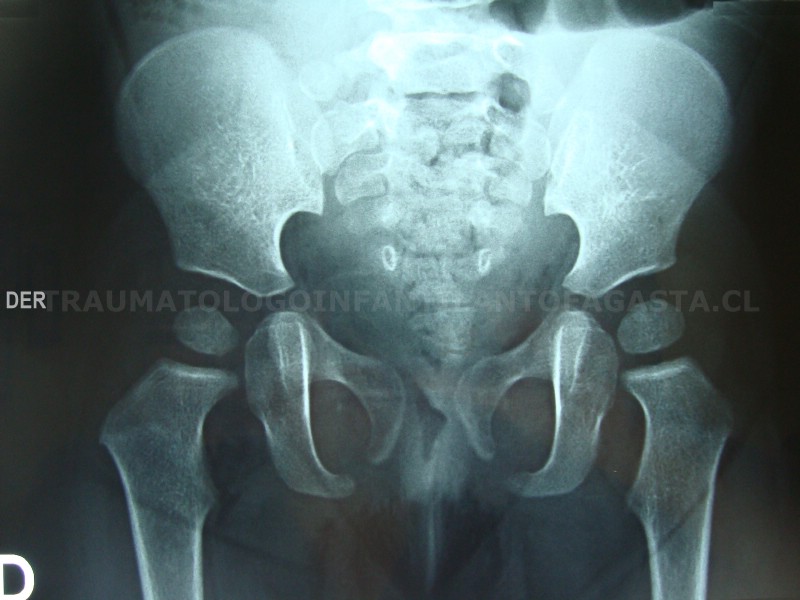

Epifisiolisis de cadera